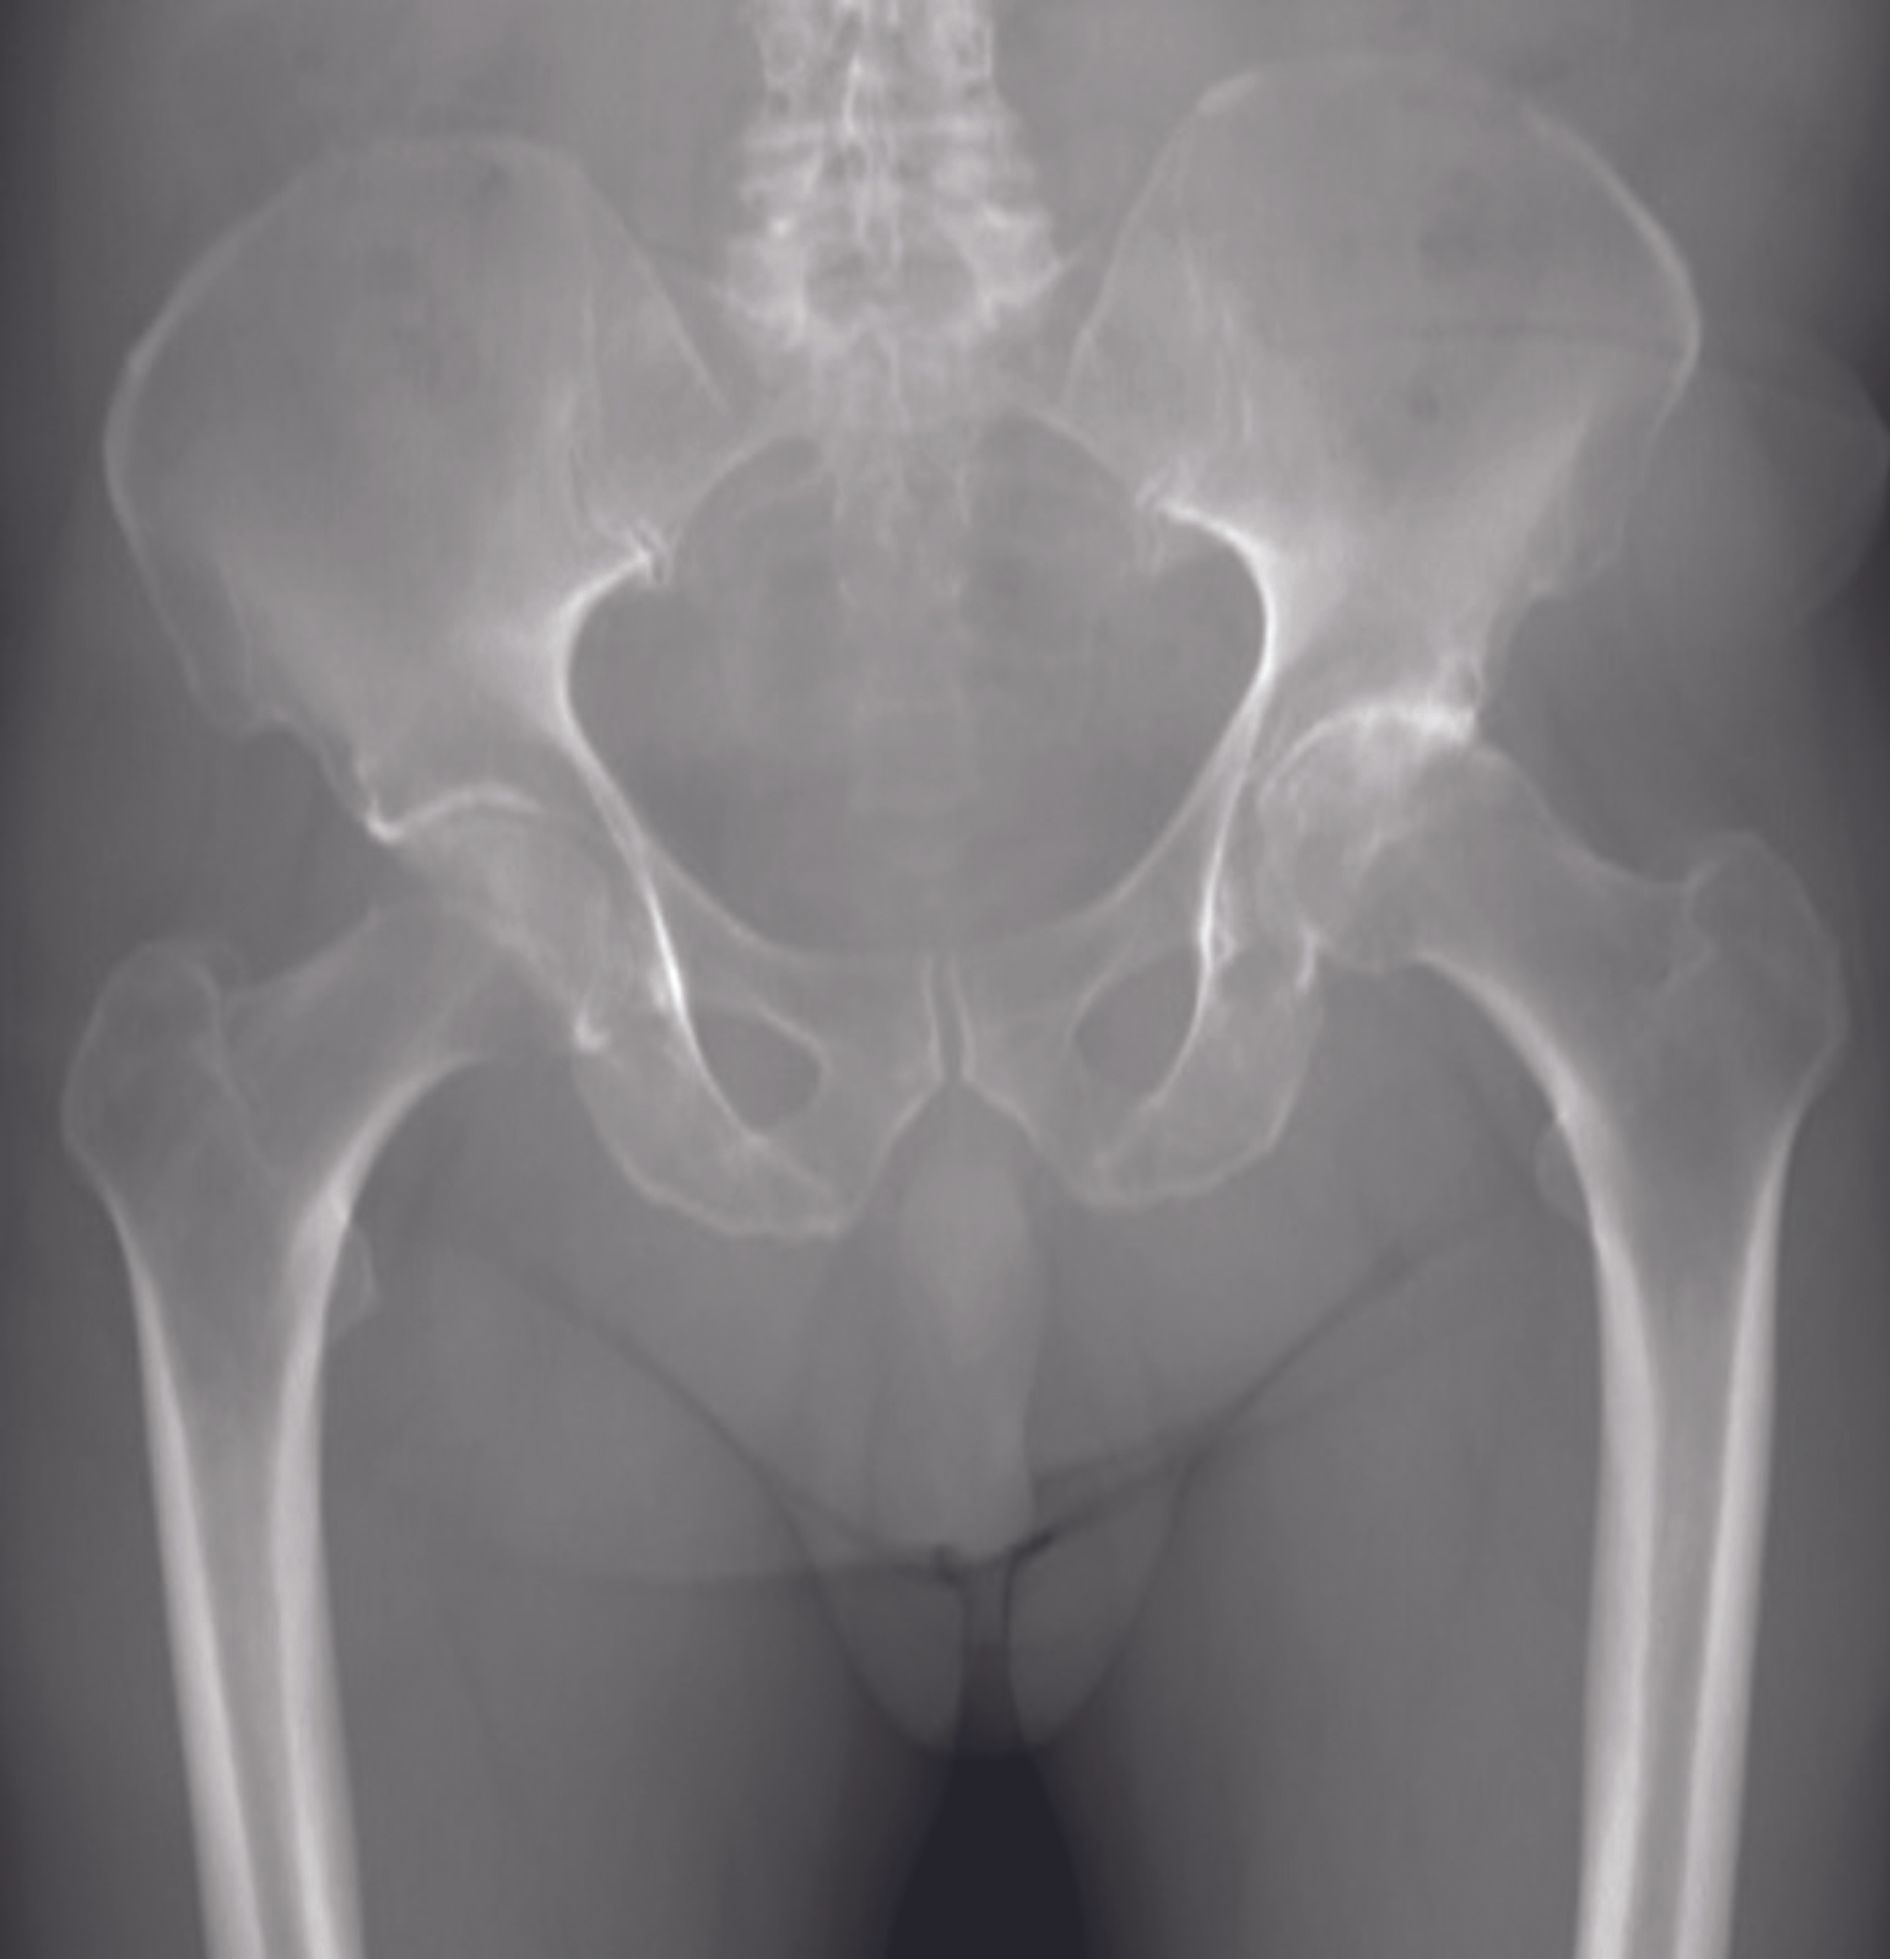

During hip arthroplasty (THR) implantation, restoration of the femoral lever arm (offset) is a crucial element in order to maintain the stability of the prosthetic joint, improve joint amplitudes and optimize the efficiency and power of the gluteal muscles [1,2]. This last point is essential, especially when the implantation is performed on a population of young subjects who wish to resume their sports activities. Indeed, adequate gluteal tension is essential for resuming activities such as running or sports with impulses on the lower limb. A value of 40 mm is commonly accepted as the upper limit of the mean femoral offset [2]. Hips with a high lever arm are very frequently accompanied by a long femoral neck and are most often found in young men and rarely in women. This is referred to as "long-neck coxa vara".

Prosthetic replacement of these hips with increased femoral offset and long necks is difficult, because it exposes the patient to many risks: instability, lameness, lengthening to tighten the gluteals and unevenness of length, and muscle failure if the offset is not restored [2]. Few non-modular femoral pivots can restore an offset of more than 40 mm. When this is possible with specific stems with a reduced neck-shaft angle, the survival rate of these implants does not seem to be as favourable as the standard offset version, because of the increase in the varus femoral moment. Other options exist: custom-made implants, short stems, trochanterotomy for distalization and re-tensioning of the gluteals, hip resurfacing (HRT), etc. The latter, which we use on a daily basis in the department, seems in this context to represent an attractive alternative, since it allows automatic reconstruction of the joint morphology. The HTR has many theoretical advantages over conventional total hip replacements: preservation of the femoral bone stock, integrity of the femoral shaft, no risk of significant elongation (variations being < 5 mm) and instability, ease of subsequent revision surgery, resumption of sports with impact, etc. [3]. Furthermore, it should be remembered that the frontal position of the femoral THR implant should be slightly valgus (7°) in relation to the native neck angle. Thus, a THR implanted on a hip in 114° vara will have a frontal position of about 120°. This valgus position transforms the shear forces into compression forces exerted on the femoral neck, which appears to be beneficial from a biomechanical point of view and for the durability of the femoral fixation.